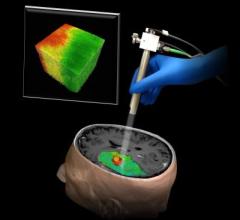

When removing a tumor, neurosurgeons walk a tightrope as they try to take out as much of the cancer as possible while keeping crucial brain tissue intact — and visually distinguishing the two is often impossible. Now Johns Hopkins researchers report they have developed an imaging technology that could provide surgeons with a color-coded map of a patient's brain showing which areas are and are not cancer.